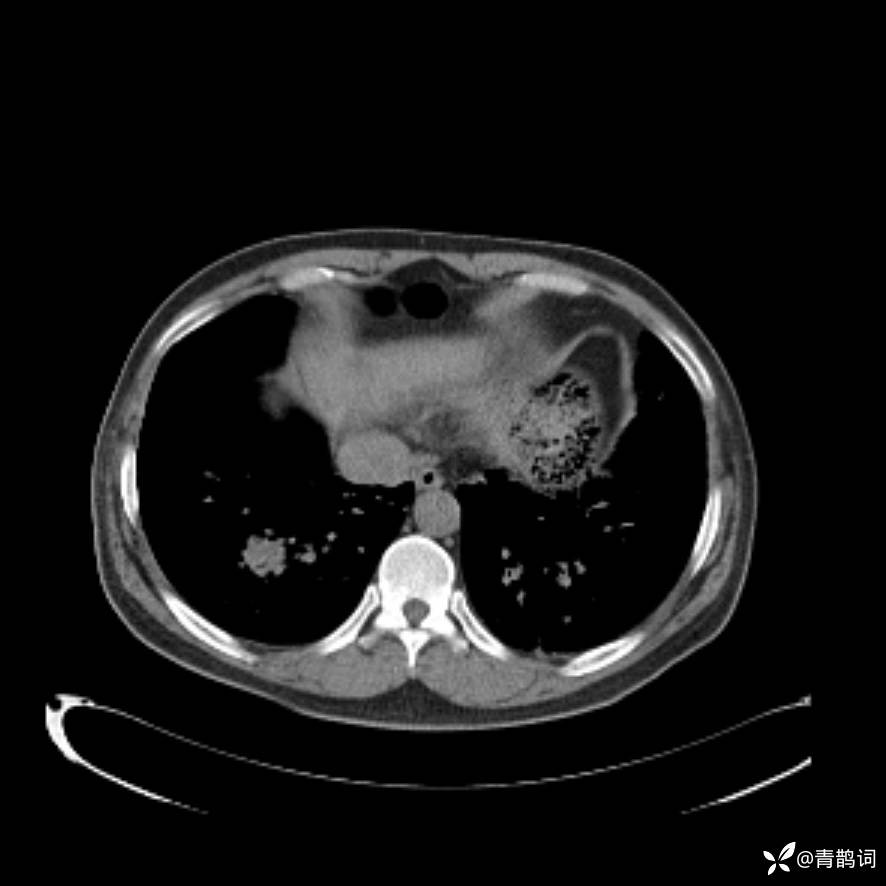

患者年龄:30岁。

患者性别:男。

简要病史:左颜面部肿胀2年,反复咳嗽咳痰,逐渐加重。

辅助检查

结合病史及影像学表现,期待评论区各位老师各抒己见~